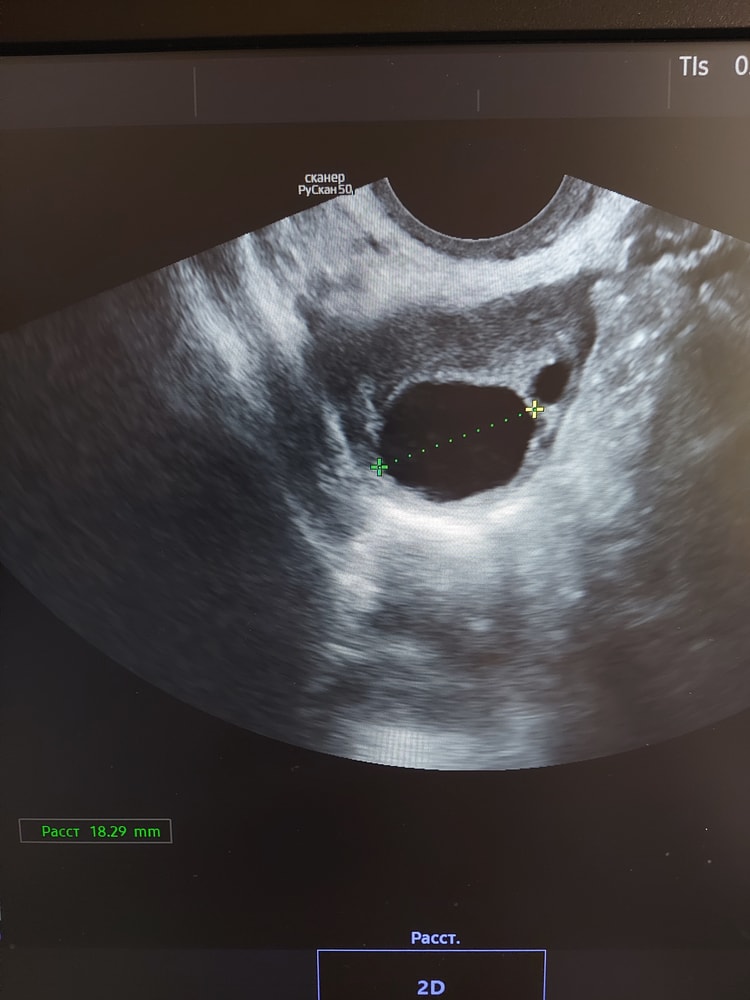

Узи на 15 день цикла показало эндометрий 8 мм и доминантный фолликул 18 мм. Сегодня 17 день цикла и узи показало ту же картину. Обычно цикл у меня 26-28 дней. Может ли фолликул перестать расти перед овуляцией?

Сегодня утром тест на овуляцию показал 2 одинаковые полоски.